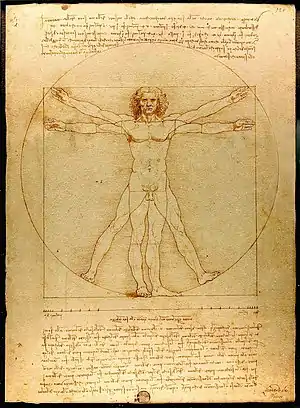

Medicine is the science and practice of caring for a patient, managing the diagnosis, prognosis, prevention, treatment, palliation of their injury or disease, and promoting their health. Medicine encompasses a variety of health care practices evolved to maintain and restore health by the prevention and treatment of illness. Contemporary medicine applies biomedical sciences, biomedical research, genetics, and medical technology to diagnose, treat, and prevent injury and disease, typically through pharmaceuticals or surgery, but also through therapies as diverse as psychotherapy, external splints and traction, medical devices, biologics, and ionizing radiation, amongst others.

Medicine has been practiced since prehistoric times, and for most of this time it was an art (an area of creativity and skill), frequently having connections to the religious and philosophical beliefs of local culture. For example, a medicine man would apply herbs and say prayers for healing, or an ancient philosopher and physician would apply bloodletting according to the theories of humorism. In recent centuries, since the advent of modern science, most medicine has become a combination of art and science (both basic and applied, under the umbrella of medical science). For example, while stitching technique for sutures is an art learned through practice, knowledge of what happens at the cellular and molecular level in the tissues being stitched arises through science.